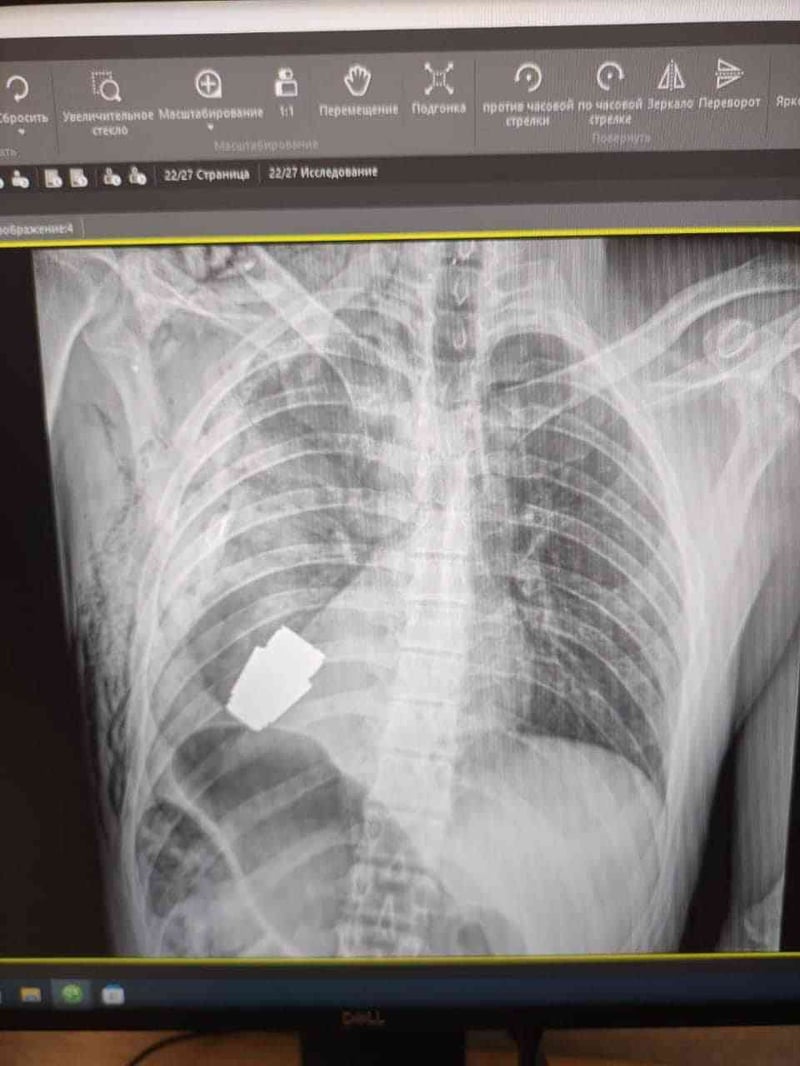

Там розповіли, що військові лікарі видалили гранату ВОГ, що не розірвалася, з тіла військовослужбовця. Її було видалено у присутності двох саперів, які страхували безпеку медичного персоналу.

Операція проводилася одним з найдосвідченіших хірургів ЗСУ – генерал-майором Андрієм Вербою без електрокоагуляції, оскільки граната могла детонувати у будь-який момент.

Оперативне втручання пройшло успішно, а пораненого військовослужбовця було відправлено на подальшу реабілітацію та відновлення».